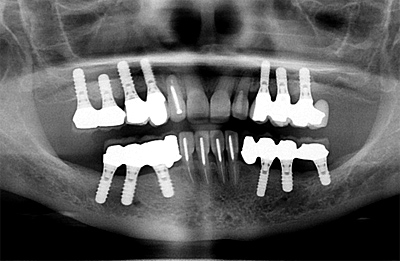

御存知の通り「インプラント治療」とはチタン合金のネジを顎骨に埋めて、その上に「歯」のようなものを載せ、その「人工の歯」を使って咀嚼を助ける治療のことです。「歯が1本抜けたらインプラントを1本埋める」のように1対1が理想です。インプラントが使われるまでは「ブリッジ」という治療法が一般的でした。なぜ「一般的」なのかと言えば、選択肢が取り外し式の「入れ歯」か、固定式の「ブリッジ」しかなかったからです。「入れ歯」は患者さんに嫌われました。下顎の入れ歯の場合は食事中に外れやすく、入れ歯の一部が舌の先が当たって邪魔なので、入れ歯を作ってもほとんど使われません。しかし、過大な咬合力が長期間小臼歯に懸かると徐々に歯を壊していきます。神経の死んでいる歯の場合は必ず折れます。小臼歯まで無くなればさすがに食事は困難を極めます。お友達と食事に行けば、いくら急いで食べても食べ終わるのは最後です。咀嚼せずに飲み込むので常に胃腸の具合が悪く、消化薬を常用しています。唯一の救いは、お友達と一緒に旅行に行ったときに入れ歯を外すところを見られずに済むことぐらいでしょうか。正面からの見た目だけは維持されますから、なんとか我慢できるのでしょう。

御存知の通り「インプラント治療」とはチタン合金のネジを顎骨に埋めて、その上に「歯」のようなものを載せ、その「人工の歯」を使って咀嚼を助ける治療のことです。できれば「1本歯が抜けたら1本インプラントを埋める」ように1対1の方法が理想です。インプラントが出るまではブリッジという治療法が一般的でした。選択肢が取り外し式の「入れ歯」か、固定式のブリッジしかなかったからです。しかし、一番後ろの歯がなくなると入れ歯しかありませんでした。特に下顎の入れ歯の場合は食事中に外れやすく、入れ歯の一部が舌の先が当たって邪魔なので、入れ歯を使わなくても食事できる場合はほとんど使われません。大臼歯2本無くても充分に食事はできます。しかし、過大な咬合力が長期間小臼歯に懸かると徐々に歯を壊していきます。生きている歯は折れることはありませんが、神経の死んでいる歯の場合は必ず折れます。小臼歯も無くなればさすがに食事は難しくなります。お友達と食事に行けば、急いで食べても食べ終わるのは最後です。そして常に胃腸の具合が悪く、消化薬を常用しています。唯一の救いは、お友達と一緒に旅行に行ったときに入れ歯を外すところを見られずに済むことぐらいでしょうか。正面からの見た目だけは維持されますから、なんとか我慢できるのでしょう。斜め45度じゃバレます。

そういう経験をしていた私の前に衝撃的な論文が出てきました。下顎半分をチタン製のインプラントでブリッジにした症例がすでに治療後10年の経過があるという話です。この論文は歯周病の世界的な雑誌に投稿されたもので、これ以前に総義歯の患者さんの治療をしたケースが多数あるようでした。これがブローネマルクインプラントの最初のタイプです。いろいろと細かな問題はありましたが、画期的な製品です。しかし、なぜこれだけ15年もOKなのか??という疑問が湧いてきました。象牙をインプラントに使うのと同じレベルでステンレスや金合金も考えられるわけですが、全く成功していません。整形外科領域では骨に使ったステンレスのネジはある意味で「自動的」にはずれます。このインプラントの開発者であるブローネマルク先生は歯医者じゃなくてお医者さんです。彼はラットの足の骨にチタン製の小さなモノサシを埋め込んで実験していたのだそうです。実験が終わって、ものさしを回収しようとしたら、骨と張り付いてしまい、骨からはずすのに苦労したのだそうです。普通ははずして終わりになるところを「人工歯根」という商品まで作り上げるところがさすがです。数年前に最初に人工歯根として治療した患者さんが亡くなり、記録はそこでストップしましたが、41年間でした。まさに「一生使えた」わけです。

すでに1000本以上(もうわからなくなりました)、19年の経験の中で大切なことがいくつか見えてきました。ひとつはハイリスクな患者さんがいることです。これは歯周病のリスクと近いものがあります。喫煙、歯周病、糖尿病などです。二つ目は埋める場所が無い人がいることです。その場合、大がかりな手術が必要になります。失敗する可能性も出てきます。三つ目は噛む力のコントロールが難しい。咬合力が出るので、反対側の歯を壊してしまう可能性があります。対合歯が入れ歯の場合、顎の骨の吸収が早くなり,入れ歯が不安定になります。四つ目は噛み合わせの問題が出てくる可能性が高くなります。今までは入れ歯だから適当に外れたりして問題が深刻化しなかったのですが、インプラントの場合は脱落がありません。だから、常に咬むことで24時間筋肉の異常が起こり、咬合に起因する問題を起こす可能性が高くなります。まあ、噛み合わせの問題はインプラントだけの問題じゃありませんけど・・・。